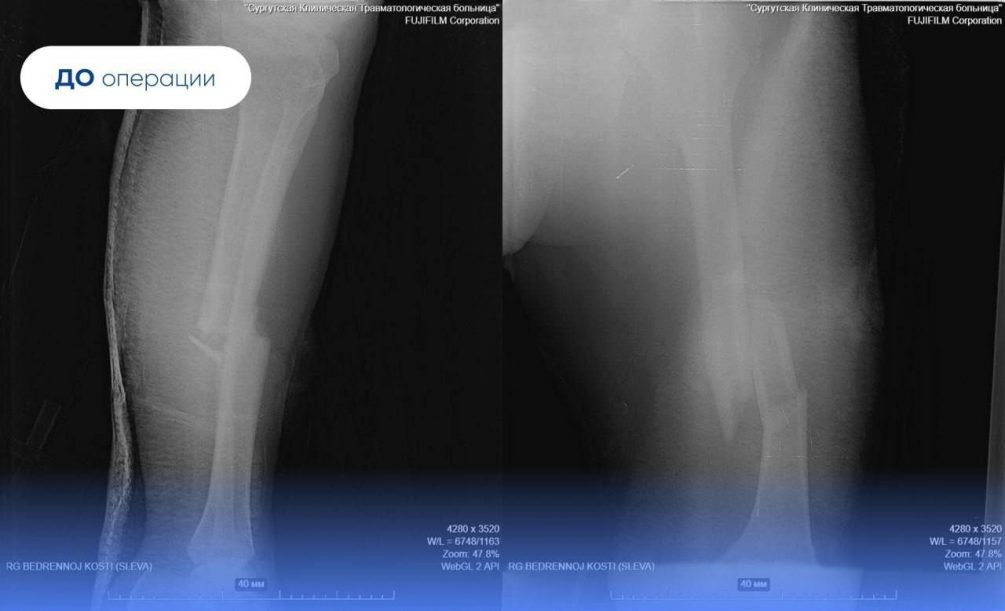

Россиянина доставили в Сургут вертолётом Центра медицины катастроф. У пострадавшего зафиксировали множественные, в том числе открытые переломы бедренной и большеберцовой костей, а также обширные раны с разрывом сосудов. Врачи отметили, что из-за этого вахтовик мог остаться без ноги.

Однако травматологи-ортопеды пришли на помощь раненому и устранили эту угрозу. Медики восстановили кровоснабжение, стабилизировали переломы с помощью временного аппарата внешней фиксации. Мужчину готовили к операции в реанимационном отделении целых два дня.

Как рассказал заведующий отделением травматологии и ортопедии учреждения Сергей Глиняный, медикам нужно было избежать хирургической агрессии и дополнительной нагрузки на организм пострадавшего. Они решили провести так называемый интрамедуллярный остеосинтез.